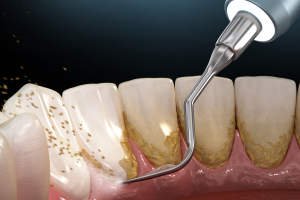

- Your dentist will then use a scaler, which is a small, hand-held tool, to remove plaque and tartar from the surfaces of your teeth, both above and below the gumline.

- In some cases, your dentist may use an ultrasonic scaler, which uses high-frequency sound waves to break up and remove plaque and tartar.